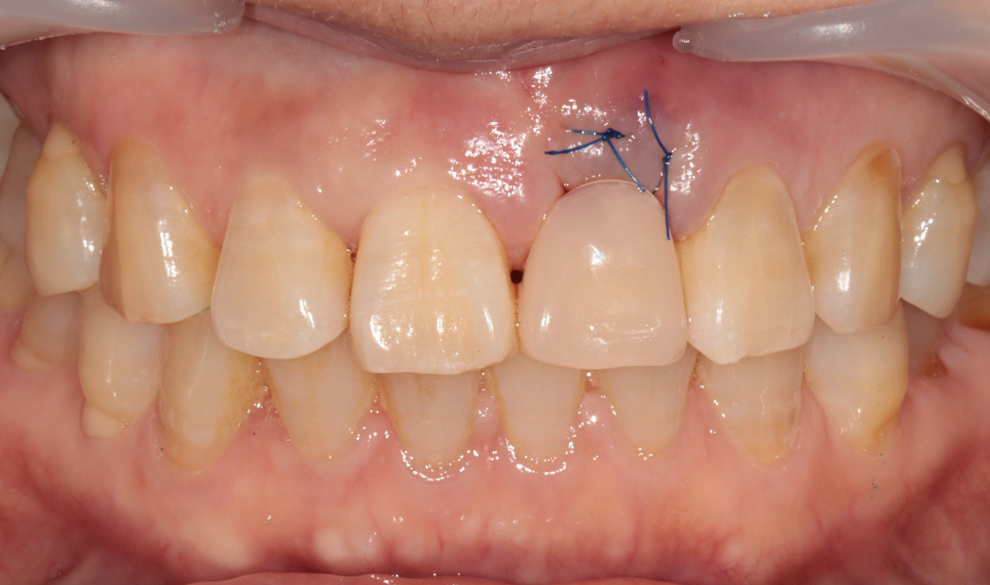

처음 내원하셨을 때의 상태입니다. 앞니 파절로 인해 치료가 시급한 상황이었습니다.